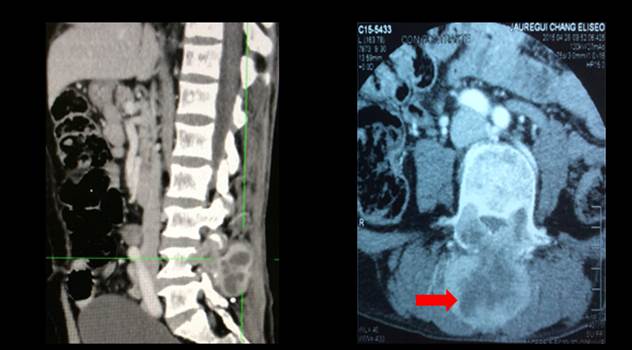

En la TEM de columna lumbosacra (figura 3) se informó lesión neoformativa que comprometía los pedículos, apófisis articulares y espinosas de L4 con densidad de partes blandas, tenía efecto expansivo, de contornos definidos con captación heterogénea del contraste que comprimía el saco dural posterior y las neuro foraminas de L4 – L5 ocasionando severa estenosis.